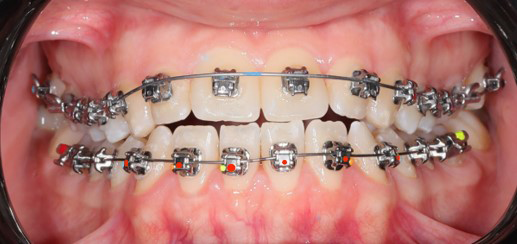

A 22-year-old female patient presented with a Class III malocclusion. She does not like her own profile. Her facial profile was straight with a slightly retrusive maxilla, the upper incisors were within normal inclination, and the lower incisors were retroclined. Bolton discrepency is on mandible for 6 teeth. A retruded upper lip and a normally positioned lower lip were noted. There was also a marked lack of midface support, and the constricted dental arches resulted in a narrow smile and pronounced dark buccal corridors.

Initial leveling in the maxillary arch was carried out with a 0.014 CuNiTi archwire. This was followed by a 0.018 CuNiTi wire, with stoppers positioned mesial to the molars and activated to provide protrusion of incisors. The mandibular arch was then bonded and initial alignment was achieved with a 0.014 CuNiTi wire, then both jaws are progressing to 0.014 × 0.0275 CuNiTi and subsequently 0.018 × 0.0275 CuNiTi for torque control.